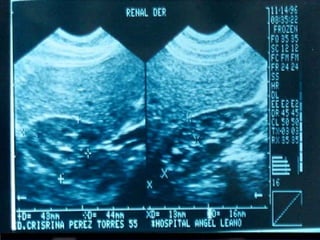

SONOGRAMA ABDOMINAL EVALUACIÓN HIGADO SISTEMA BILIAR BAZO  RIÑONES PANCREAS ( no específico)

SONOGRAMA ABDOMINAL EVALUACIÓNHIGADO SISTEMA BILIAR BAZO RIÑONES PANCREAS ( no específico)